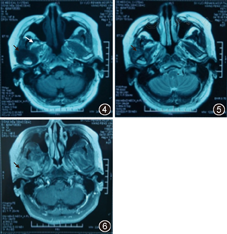

右颞下颌关节有一不规则钙化高密度灶,呈哑铃形。外侧部分类似球形,突破关节腔位于颧弓下方、乙状切迹外侧及髁突前方;中间部分沿关节腔分布,呈盘状,与关节面间有潜在间隙,患例关节腔较健侧明显增宽;内侧部分跨越关节结节向前内斜形进入颞骨鳞部和蝶骨岩部,颅底骨质破坏(图1,图2,图3)。